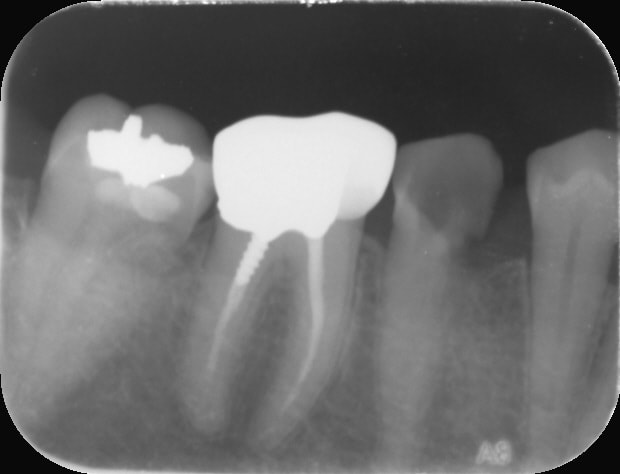

Tiens celle ci c'est pour le plaisir d'offrir et c'est pour Vulpi qui avait l'air de se moquer de moi hier😊:

-> cas d'aujourd'hui

- dent calcifiée comme jamais

- je réussis à retrouvé le canal au niveau des 3/4 de la dent avec un insert endo fin (radio avec insert ci joint)

- obturation quasi Ă  l'apex

- rĂ©alisĂ© avec un capodent et non une digue😊😊😊

Ah c'est dommage! La 6 a une couronne non adaptée en distal (premiÚre RX il y a la reconstitution qui déborde, c'est pas étanche) et probablement une indication de RTE, la 5 non conservable à long terme, 4 en pilier antérieur dent vivante, voilà une belle indication de bridge :-)))